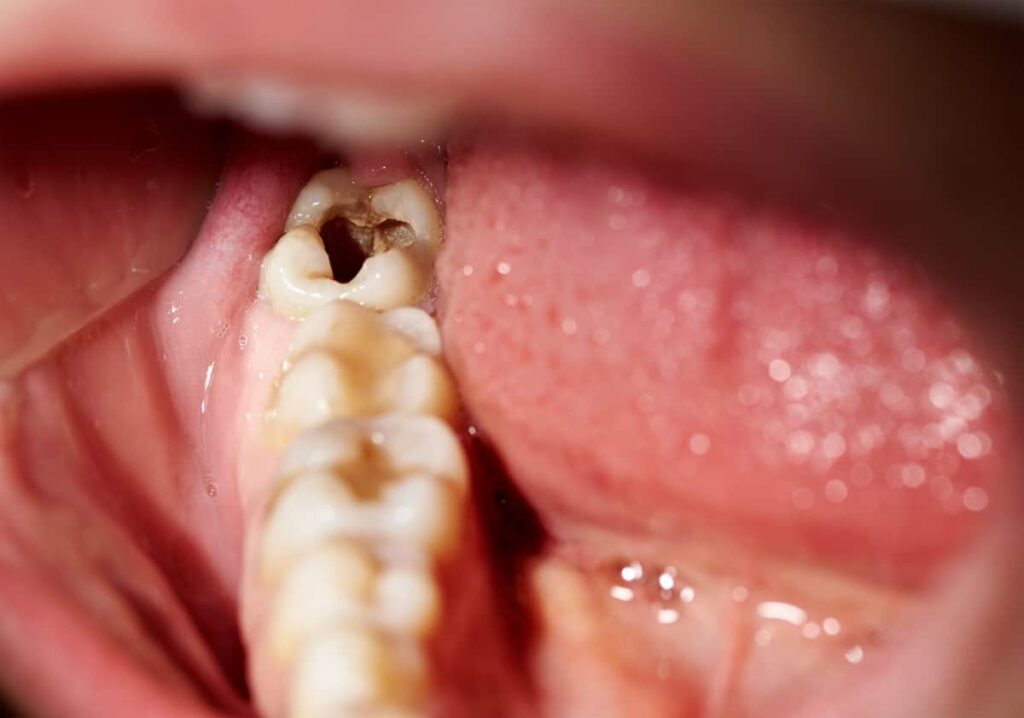

What Counts as a Dental Emergency?

If you’re unsure whether you need immediate care, here are the most common dental emergencies we treat:

| Severe toothache or pain | Yes |